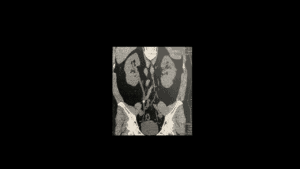

Cálculos Urinários